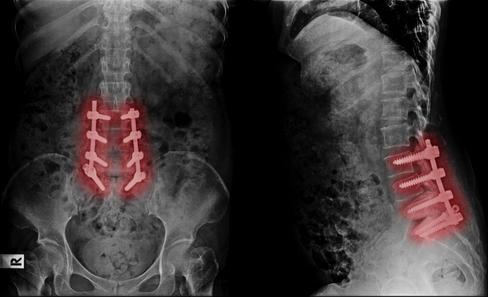

an fusion, screws, egenerative

moments. Stop d pain mean fusion, screws, e l d

your last stop

e